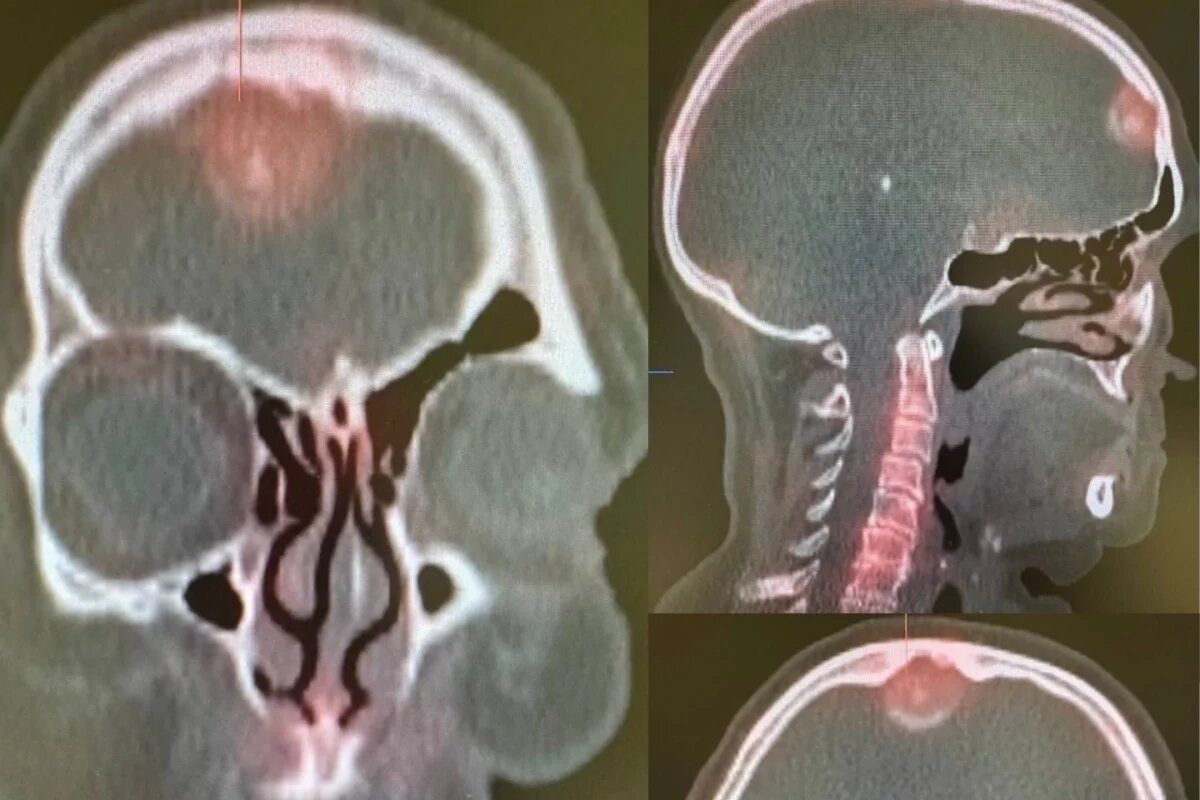

Сцинтиграфия позволило выявить у неё очаг гиперфиксации радиофармацевтического индикатора в лобной области. Для более точной визуализации выявленных изменений пациентке сделали ОФЭКТ-КТ исследование. В ходе обследования онкологи выявили в голове женщины новообразование, которое плотно прилегало к лобной кости.

«Для более детального изучения новообразования было рекомендовано провести магнитно-резонансную томографию головного мозга с внутривенным контрастированием. Более четкие изображения при данном исследовании позволили дифференцировать новообразование от метастатического поражения и помогли врачу выявить менингиому», – подчеркнули в Псковском онкологическом диспансере.